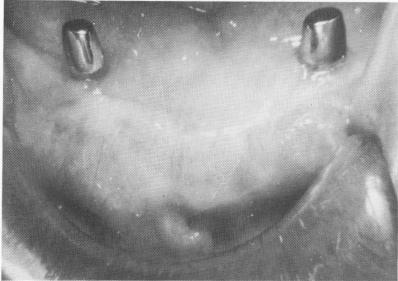

Fig. 12-31. A temporary acrylic stent obtained from a surgical bone bite is fabricated.

If a new denture is made, it need only have six anterior acrylic teeth and two posterior acrylic occlusal tables (Fig. 12-31) . No matter which denture is used, it should be tried in the mouth and balanced. The denture should not be in premature occlusion; the bite should not be beyond the original vertical dimension. Fast-setting acrylic should be mixed and placed inside the denture, which is then placed into its proper position over the four implant abutments, and the patient is asked to bite into centric occlusion.

2 Temporary acrylic stent obtained from surgical jaw bone bite prepared